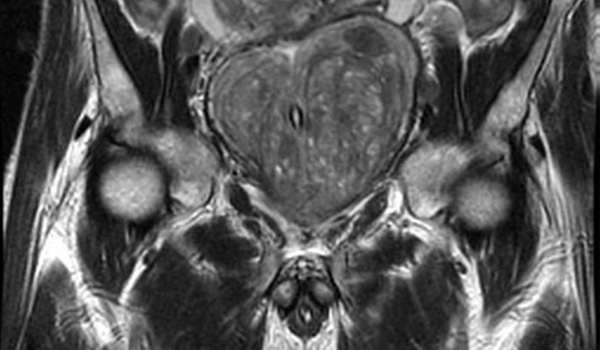

Imágenes por resonancia magnética en la detección del cáncer de próstata: revisión sistemática y metanálisis

Los resultados de esta revisión sistemática y metanálisis sugieren que la integración de la resonancia magnética en las vías de detección del cáncer de próstata se asocia con un número reducido de biopsias innecesarias y un sobrediagnóstico de cáncer de próstata insignificante, al tiempo que se mantiene la detección de cáncer de próstata clínicamente significativo en comparación con la detección solo con PSA. JAMA Oncol, 5 de abril de 2024